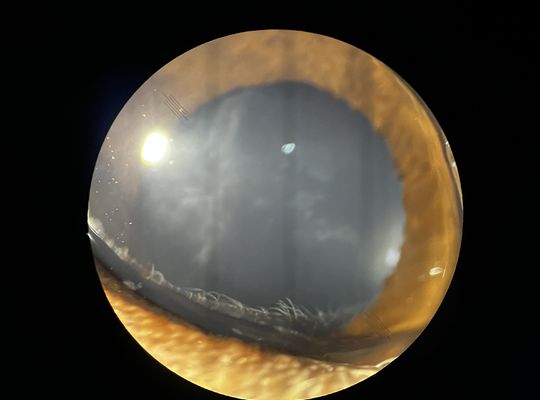

• 白内障と小夏の両親と兄妹

先月 小夏が白内障を患ってたという事を このプログで報告しました。そして 点眼液を1日5回とサプリメントを飲ませています。  妹の白内障発覚で 小夏も白内...

• 6歳の誕生日と 眼の病気

小夏は 9月6日の誕生日を迎えて、6歳となりました。 まりりんが 糖尿病性白内障を患い、眼が見えなくなり、悪いことしたなあと 常々 思い、小夏も10歳過ぎたら、...